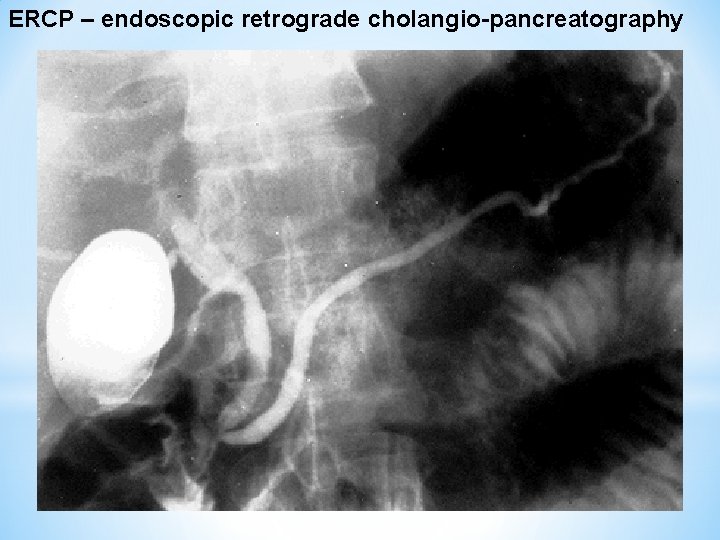

ERCP – endoscopic retrograde cholangio-pancreatography